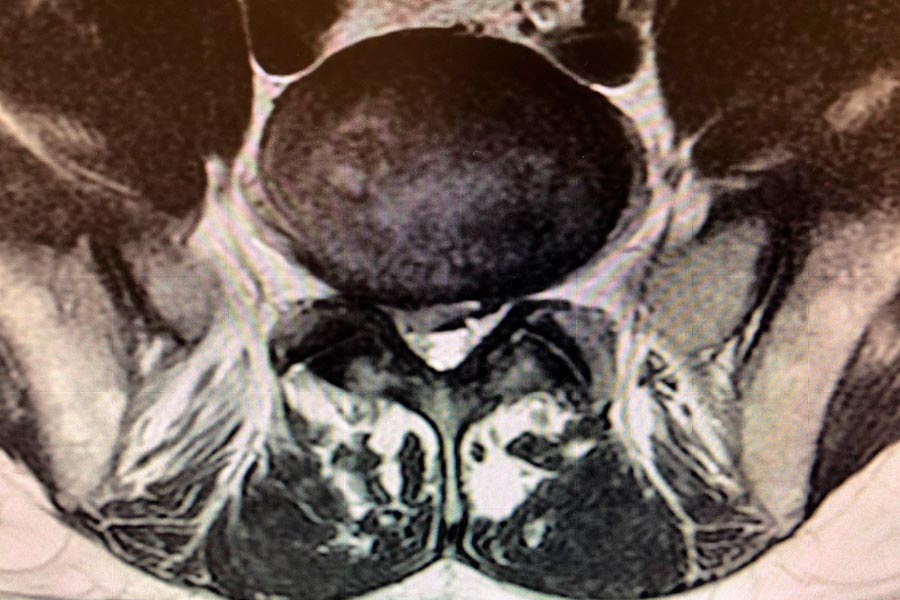

Caso clínico de Hernia en el disco L5S1 lateralizada

Hernia discal lateralizada

En este caso, el Doctor Elgeadi se encarga del tratamiento, con una tecnica de cirugía mínimamente invasiva, de localizar y extraer una hernia discal, de pequeño tamaño en la L5S1.

A pesar de que el tamaño de la hernia es bastante pequeño, el paciente sufre molestias en el tren inferior, con dificultades a la hora de caminar o hacer esfuerzos con las piernas.

cirugia-discal-mínimamente-invasiva